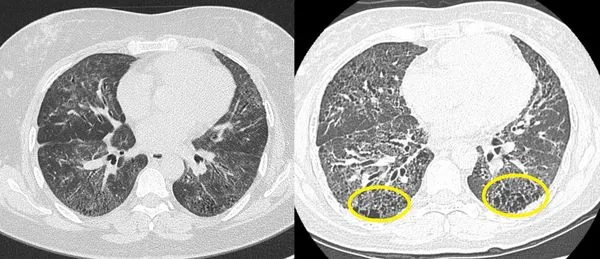

▲蔡秉翰指出病人發病初期下半肺部出現發炎與浸潤(左圖),後期進展為纖維化形成蜂窩狀之空洞(右圖)。(圖/土城醫院)

蔡秉翰指出,結締組織疾病相關間質性肺病的發生,通常是因為自體免疫反應所引起的肺部間質病變,主要是免疫系統攻擊正常的肺部細胞,導致肺部間質(即肺泡與血管之間的結締組織)發炎和纖維化,進而使肺部的氣體交換功能受損,嚴重則會合併急性呼吸困難。